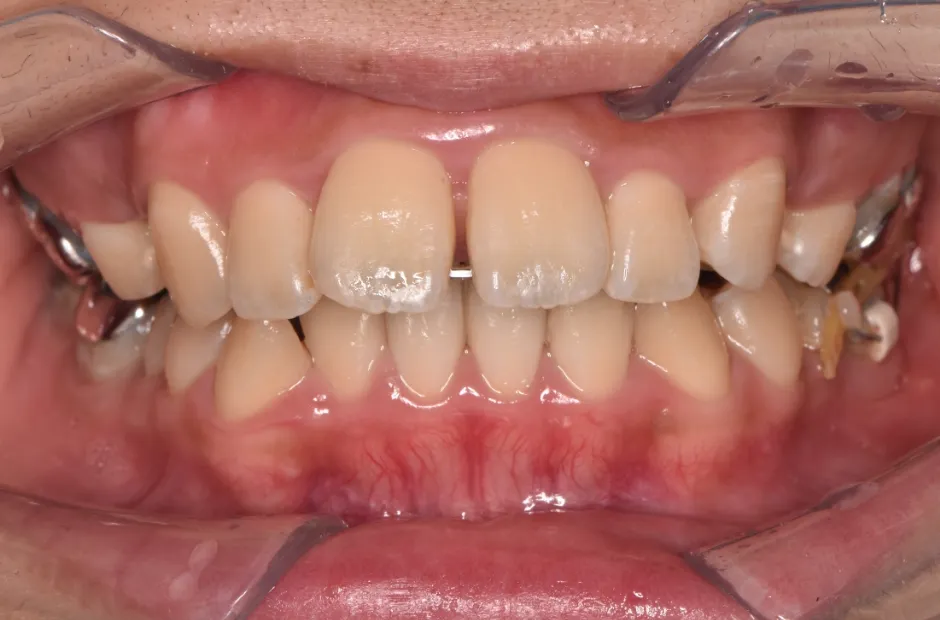

叢生

| 診断名・主訴 | 叢生 |

|---|---|

| 年齢・性別 | 43歳・女性 |

| 治療期間・回数 | 2年7か月 27回 |

| 治療に用いた主な装置 | 舌側矯正 |

| 抜歯部位 | 両顎4,4 |

| 治療費 | 100万円(税抜) |

| リスク・副作用 | 装置による違和感・疼痛・歯肉退縮・歯根吸収・虫歯のリスクなど |

治療中

治療後